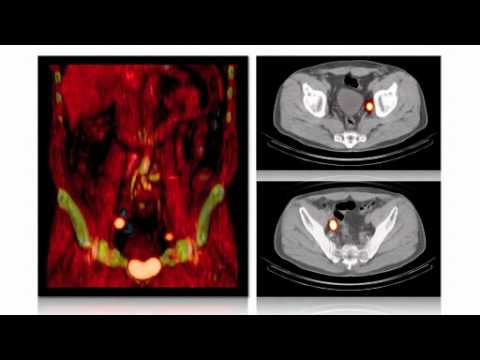

Cyber Laser Ablation Of Prostate - YouTube

Joel D. Lilly, M.D. - YouTube